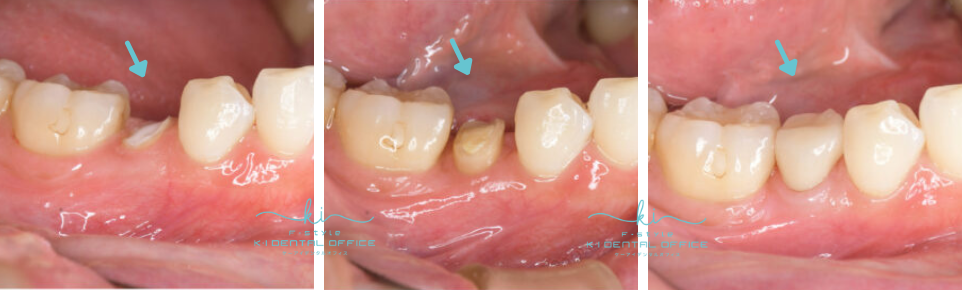

移植前

重度虫歯の右上6番の歯に、右上の親知らず(8番目)を移植しました。

移植後